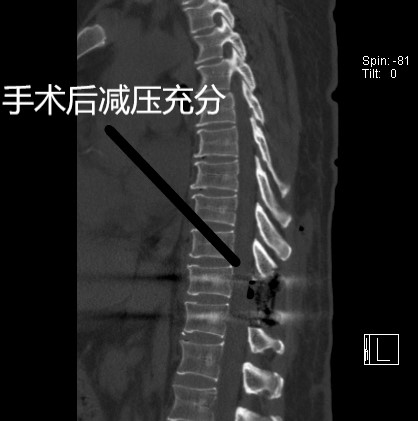

患者入院后朱亮博士结合检查结果,决定实施“揭盖式”胸椎后壁切除内固定术。手术中朱博士用高速磨钻沿双侧关椎弓根内侧连线,磨透椎板全层、关节突及骨化的黄韧带,直至硬脊膜侧壁外露。用巾钳夹住棘突、椎板及关节突一部分轻轻向后提拉,同时用神经剥离子分开骨化韧带与硬脊膜间的粘连,将椎板及骨化韧带整体切除。历时6小时手术顺利结束,无硬膜囊撕裂,无脊髓神经损伤。术后第二天患者下肢麻木等症状明显缓解。术后一周便佩戴腰围下床活动,目前已顺利出院。

术中照片见手术减压充分,硬膜囊膨隆满意。

手术后的影像学检查